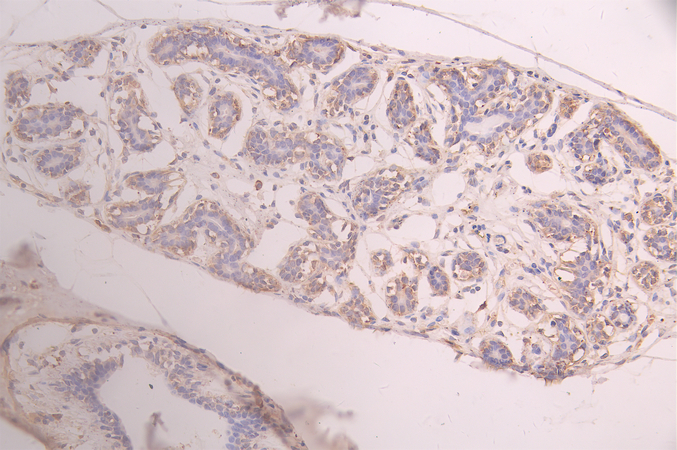

IHC image of CSB-RA732978MA1HU diluted at 1:100 and staining in paraffin-embedded mouse testis tissue performed on a Leica BondTM system. After dewaxing and hydration, antigen retrieval was mediated by high pressure in a citrate buffer (pH 6.0). Section was blocked with 10% normal goat serum 30min at RT. Then primary antibody (1% BSA) was incubated at 4°C overnight. The primary is detected by a Goat anti-human polymer IgG labeled by HRP and visualized using 0.05% DAB.